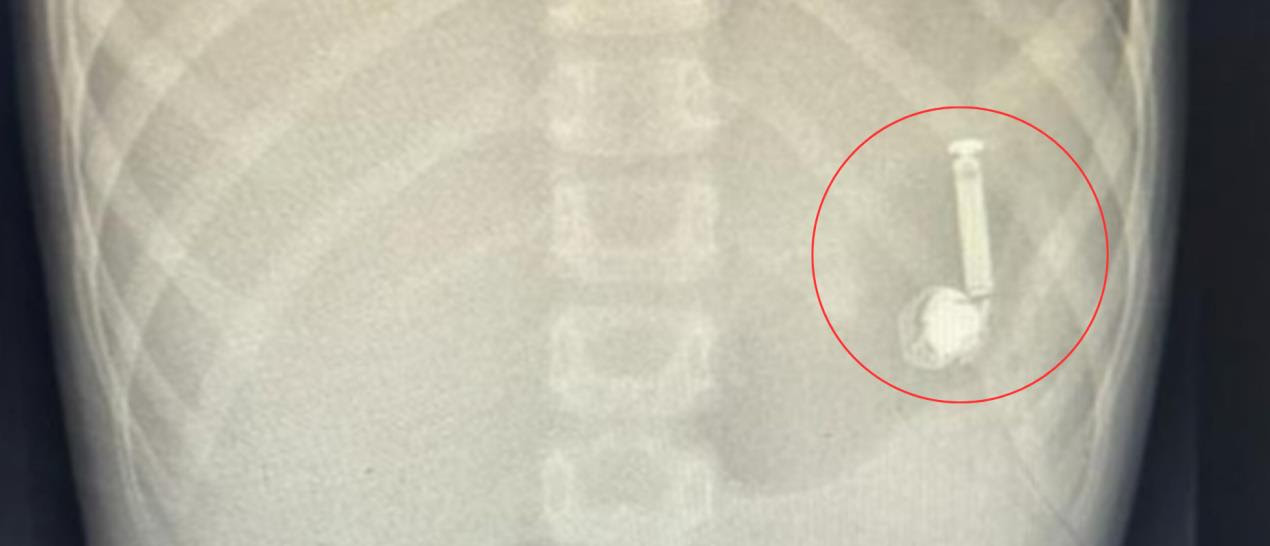

A medical team at the Maternity and Children Hospital in Makkah (western Saudi Arabia) removed a Bluetooth earphone from a 10 -year -old’s stomach.

The child arrived at the emergency department, and the family informed doctors that he swallowed the earphone. Immediately, he underwent the necessary medical examinations. A medical team from the endoscopy and the anesthesia department preformed an endoscope operation without surgical intervention.

The operation ended successfully in a short period of time and the earphone was removed. The child left the hospital in good health.